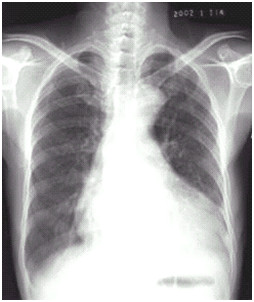

临床助理执业医师实践技能第一站【X线-胸腔积液】知识点模拟题

临床助理医师实践技能第一考站影像诊断模拟试题(2分)

临床执业助理医师实践技能第一考站【X线-肺癌】考点模拟题